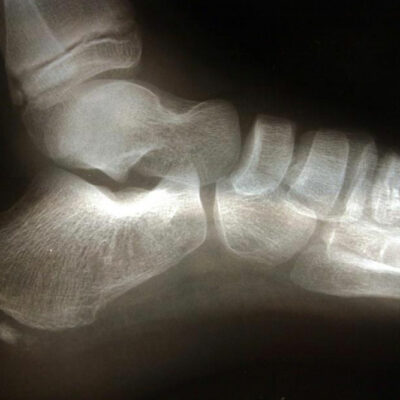

Commonly affecting athletes who frequent activities include running and jumping, heel spur is caused due to calcium deposits on the underside of the heel bone. The symptoms include inflammation of tissues and tendons near the spur, pain while walking or jogging, formation of calluses, swelling or redness of the affected part of the heel.